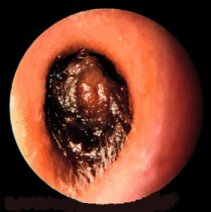

Fungal infection of the ear canal